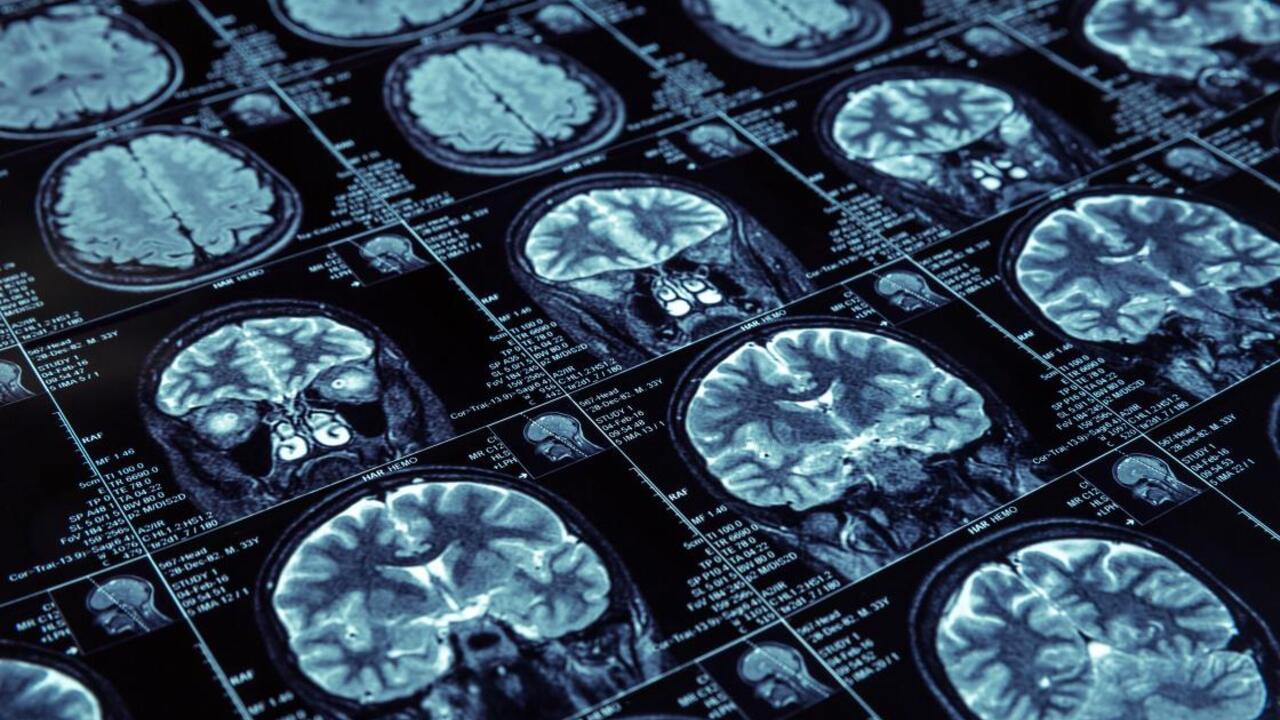

Найдена связь между особенностями мозга и риском шизофрении

По словам специалистов из Norment (норвежский центр исследования психических расстройств), группа генов, связанных с риском развития шизофрении, также оказывает влияние на размер и толщину поверхности мозга человека. Об этом говорится также в статье, опубликованной в издании JAMA Psychiatry.

По мнению экспертов, толщина и размер поверхности мозга могут являться биомаркерами шизофрении как психического расстройства. То есть после определения этих значений можно будет сказать, насколько высок риск развития у человека шизофрении.

Кроме того, в ходе проведённого исследования учёные проанализировали гены более 40 тысяч пациентов с шизофренией, а также почти 65 тысяч здоровых людей. Всю информацию взяли специалисты из европейских баз данных. В итоге они смогли доказать, что действительно существует генетическая связь между этой болезнью и особенностями поверхности мозга.